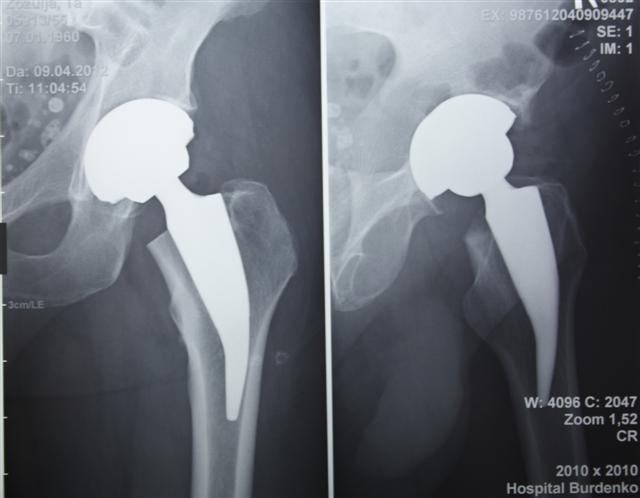

На сегодняшний день общепризнано, что эндопротезирование тазобедренного и коленного суставов является единственным эффективным методом лечения при разрушении суставного хряща и позволяет избавит пациента от боли и вернуть его к активной жизни. В мире ежегодно выполняется более полутора миллионов таких операций. Современные эндопротезы служат десятки лет и позволяют жить полноценной жизнью даже молодым и активным пациентам, а в случае, если эндопротез всё же износился, его можно заменить на более сложный и продолжать пользоваться всеми благами жизни.

Ортопедическое отделение Главного военного клинического госпиталя им. акад. Н.Н.Бурденко занимается вопросами эндопротезирования крупных суставов более 30 лет. Мы прошли весь тернистый путь проб и ошибок в освоении этой специальности, познали горечь неудач и радость успеха. В отделении разработаны и запатентованы: уникальная методика двухэтапного эндопротезирования тазобедренных суставов, новые способы костнопластического замещения значительных дефектов вертлужной впадины при ревизионных операциях.

В последние годы мы активно занимаемся проблемой эндопротезирования тазобедренного сустава у молодых пациентов, в том числе при врождённой патологии (дисплазии) используя при этом новейшие высококачественные долговечные эндопротезы.